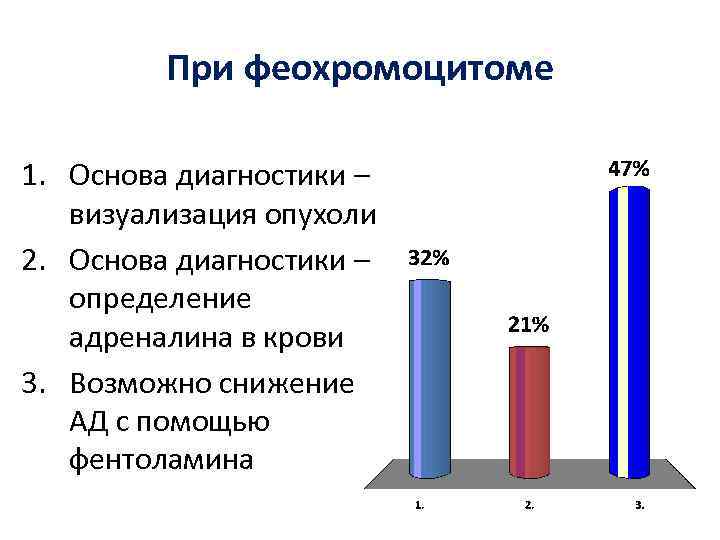

При феохромоцитоме 1. Основа диагностики – визуализация опухоли 2. Основа диагностики – определение адреналина в крови 3. Возможно снижение АД с помощью фентоламина

При феохромоцитоме 1. Основа диагностики – визуализация опухоли 2. Основа диагностики – определение адреналина в крови 3. Возможно снижение АД с помощью фентоламина